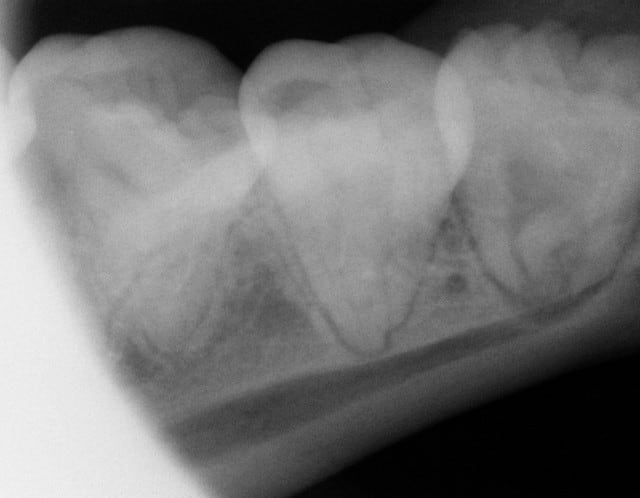

Un autre type d'application en paro du CO² est son utilisation sans photo-ablation en défocalisant à faible puissance, ce qui entraine une cautérisation avec stérilisation, décongestionnement par évaporation de l'inflammation, sédation immédiate des douleurs et biostimulation.

Un exemple la semaine dernière: une patiente de 21 ans reçue en urgence pour un accident d'éruption de la 38 ayant entrainé une névralgie et un trismus avec ouverture limitée à 22mm.

Après utilisation d'un diode HeNe AsGa en mode myorelaxation, ce qui a permis une ouverture en quelques secondes à 30mm, un tir en balayage continu du CO² à 1W a fait disparaitre instantanément la douleur et a porté l'ouverture buccale à 40mm. Le tout a pris seulement quelques minutes.

J'ai alors pu lui prendre une radio et ai poursuivi sans problème par son premier détartrage, la jeune fille étant fumeuse (10 cigarettes par jour depuis 2 ans)... je suis alors tombé sur des leucoplasies au maxillaire que je n'aurai jamais découvertes sans l'aide de mes lasers ou avec une prescription d'AB et AI sans la revoir probablement, ses dents étant impeccables.

Je les lui ai montré et ai essayé de lui faire prendre conscience des risques qu'elle prenait en continuant à fumer sans l'affoler évidemment.